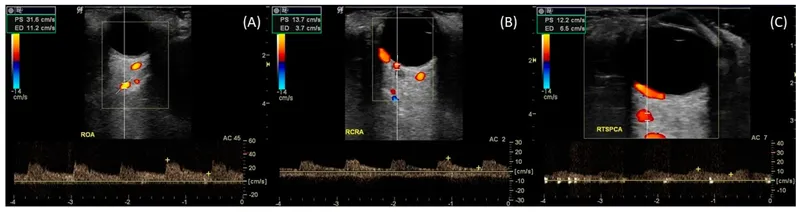

The ophthalmic artery provides 85% of orbital blood supply, branching into 10 major vessels within the 30ml orbital space. This dense vascular network creates unique hemodynamic relationships where venous congestion produces immediate clinical signs due to the orbit's rigid bony boundaries.

| Ophthalmic Artery | 50-80 | 80-120 systolic | ↓50% in giant cell arteritis | <25 ml/min = vision loss |

| Central Retinal Artery | 8-12 | 60-80 | ↓70% in CRAO | <3 ml/min = irreversible |

| Superior Ophthalmic Vein | 15-25 | 8-15 | ↑200% in AVM | >30 mmHg = proptosis |

| Posterior Ciliary | 20-35 | 70-90 | ↓40% in AION | <15 ml/min = optic ischemia |

| Lacrimal Artery | 5-8 | 75-95 | ↑300% in hemangioma | >25 ml/min = pulsatile mass |